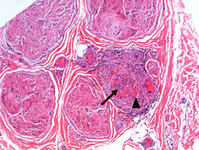

Medium-size artery and arterioles in epi- perineurium of sural nerve showing transmural dense mixed cell infiltrates, fibrinoid necrosis and luminal occlusion (arrow) in a case of polyarteritis nodosa. Note that the muscularis layer is interrupted and destroyed by the inflammatory infiltrate (arrowhead). Paraffin section; Hematoxylin and Eosin

From the personal collection of Professor Sakir Humayun Gultekin, MD, FCAP; used with permission